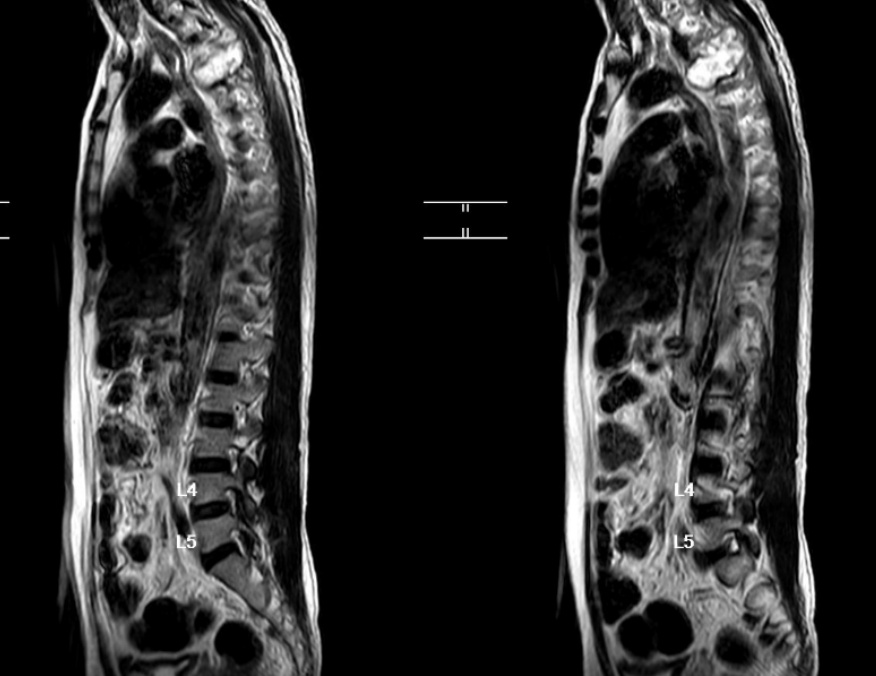

2025年2月,许先生前往台湾接受了左侧第四肋骨部分切除术,术后病理提示为软骨肉瘤。本以为这场与肿瘤的对抗已初见成效,没想术后仅半年,PET/CT 复查显示,他的左侧第四肋骨残端近胸椎侧出现了疑似肿瘤残留病灶,且已部分侵犯胸椎。同年12月,再次复查局部磁共振提示他的胸椎T4节段出现肿瘤转移,巨大的软组织肿块向椎管内延伸,严重压迫脊髓,还累及了多个椎体、肋骨与神经根,并且出现了脊髓压迫的症状——双下肢肌力开始下降,活动逐渐受限。短短两周内,他突然出现双下肢麻木伴无力的症状,紧急在新加坡当地的医院接受姑息性减压手术,可这场手术并未带来转机,反而让他的双下肢肌力降至M0级彻底瘫痪。

术前MR影像图